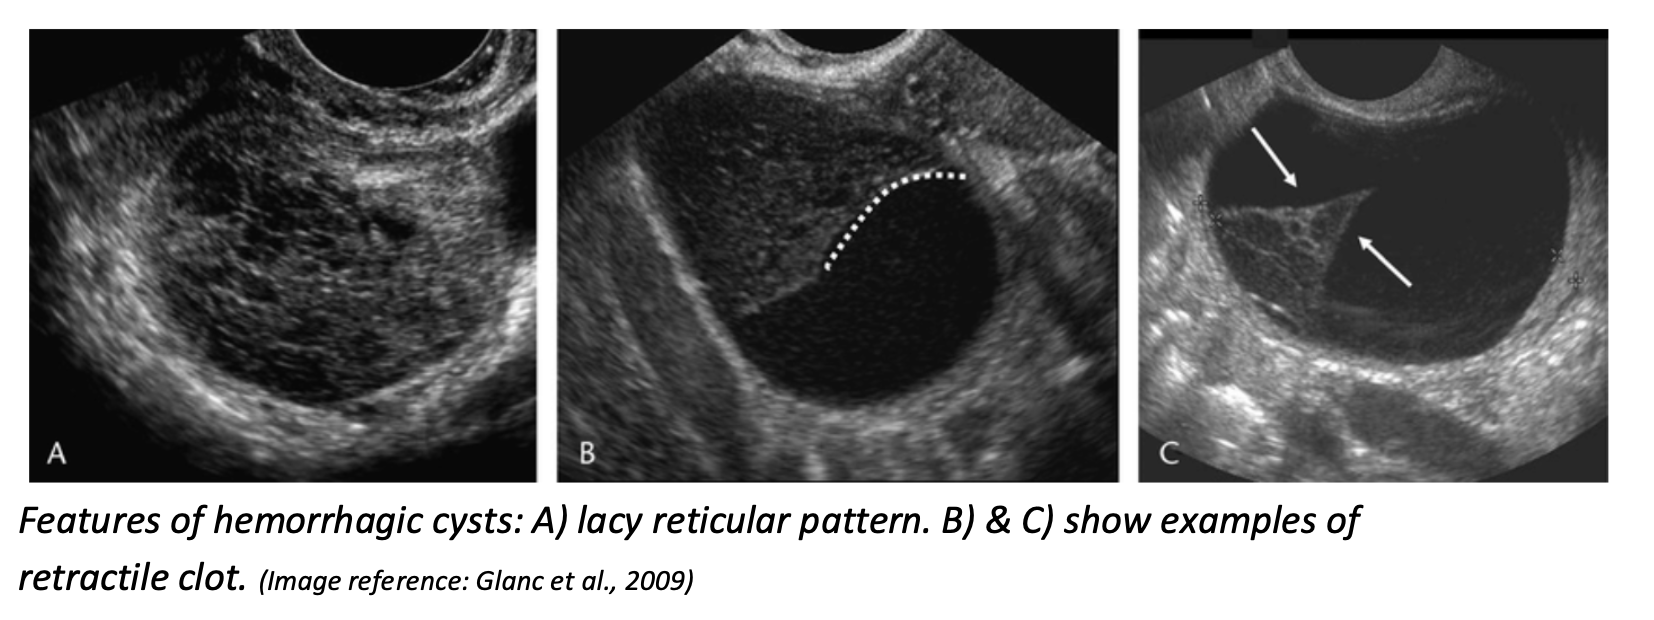

Hemorrhagic Cyst

PoCUS features

-

Reticular or “lacy” pattern of fine internal echoes (“fishnet” or “cobweb” appearance) — due to fibrin strands from clotted blood

Fluid–fluid levels (from settling of blood products)

May show retracting clot: fibrin components contract, causing a concave, sharp, curvilinear or triangular internal mass that pulls away from the cyst wall

Usually no internal Doppler flow (but circumferential wall flow may be seen)

Glanc, P., Salem, S., & Farine, D. (2009). Adnexal masses in the pregnant patient: A diagnostic and management challenge. Ultrasound Quarterly, 24(4), 225–240.